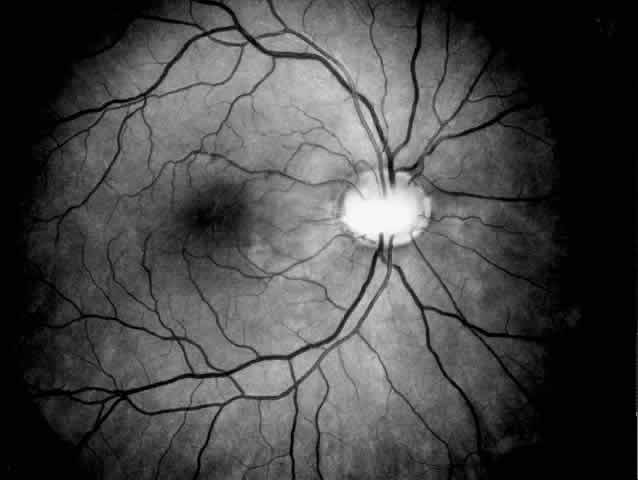

epithelium.37 Focal degeneration of the retinal pigment epithelium with patchy depigmentation

of the fundus may appear early in life and is generally present

by age 7.37 The fundus lesions are bilateral and symmetric and involve mainly the

periphery, although some patients also develop atrophic macular changes (Fig. 3). Abnormal retinal function with reduced or extinguished responses on

electroretinograms and decreased visual acuity are frequent complications

in older cystinotic patients.37,38 Several other complications have been described in patients with nephropathic

cystinosis, including superficial punctate keratopathy, recurrent

erosions, corneal vascularization, band keratopathy, tight miosis, posterior

synechiae, and pupillary-block glaucoma.35,37–39  Fig. 3. Cystinotic fundus changes in a 19-year-old patient, demonstrating a pale

optic disc and numerous peripheral and macular small white spots at

the level of the retinal pigment epithelium. Fluorescein angiography confirmed

marked degenerative changes of the retinal pigment epithelium

with macular, peripapillary, and peripheral window defects. Fig. 3. Cystinotic fundus changes in a 19-year-old patient, demonstrating a pale

optic disc and numerous peripheral and macular small white spots at

the level of the retinal pigment epithelium. Fluorescein angiography confirmed

marked degenerative changes of the retinal pigment epithelium

with macular, peripapillary, and peripheral window defects.